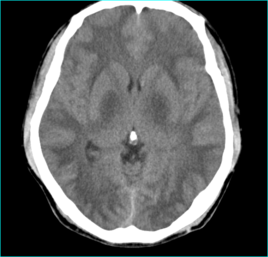

腦白質(zhì)脫髓鞘,已經(jīng)發(fā)育成熟的正常髓磷脂被破壞,即:腦白質(zhì)脫髓鞘(demyelination)疾病。它主要包括:多發(fā)硬化、進行性多灶性腦白質(zhì)病、急性散發(fā)性腦脊髓炎、亞急性硬化性全腦炎、橋腦中央髓鞘溶解癥、胼胝體變性、皮層下動脈硬化性腦病和同心圓硬化等。